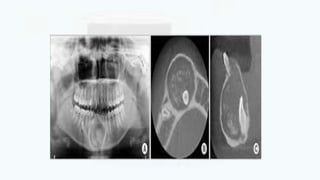

IMAGING FEATURES

 LOCATION

• the epicenter of cyst is found just above the crown of the involved

tooth,

• Important diagnostic point – cyst is attaches at the CEJ

• most commonly mandibular or maxillary 3rd molar or a maxillary

canine.

• Cysts related to maxillary 3rd molars

grow into the maxillary antrum and

may become large before they

discovered

• Cyst attached to mandibular molars

my extend a considerable distance

into ramus or lower border mandible

PERIPHERY AND SHAPE

• Typically have a well defined cortex with curved outline or circular

outline.

• If infection present, the cortex may be missing

INTERNAL STRUCTURE:

• The internal aspect is completely radiolucent except for crown of the

involved tooth

EFFECTS ON SURROUNDING STRUCTURES

• May displace and resorb adjacent teeth

• It commonly displaces the associated tooth away from its direction of

eruption

• Thus the maxillary 3rd molar may be found at the floor of the

maxillary antrum

• The mandibular 3rd molar may be found at the lower border of the

mandible and in the ascending ramus

• maxillary canine in the sinus as far as the floor of the orbit

• The slowly expanding cyst erodes cortical plates

• Cause resorption of adjacent tooth roots in 55% of cases